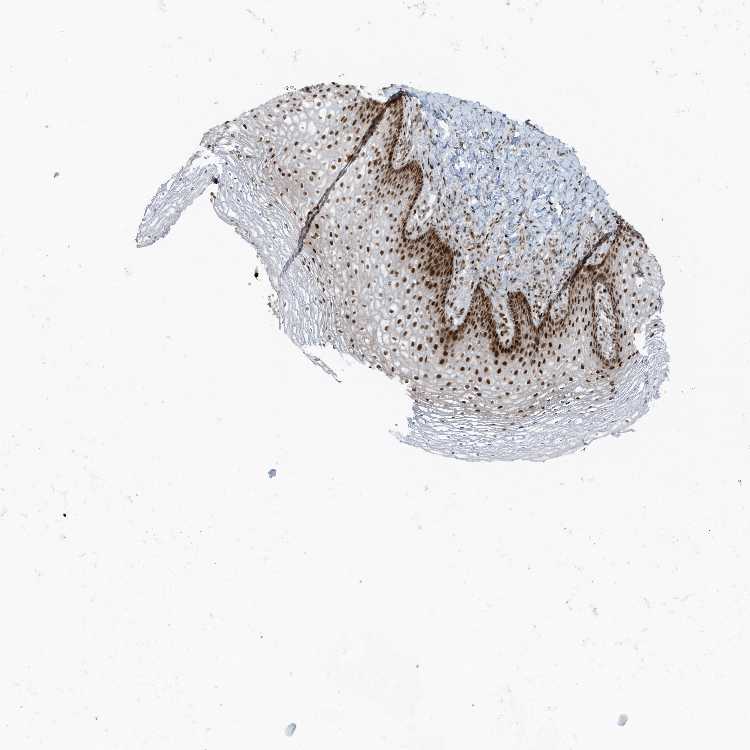

VAGINA - Antibody stainingi

Antibody staining in the annotated cell types in the current human tissue is reported as not detected, low, medium, or high, based on conventional immunohistochemistry profiling in selected tissues. This score is based on the combination of the staining intensity and fraction of stained cells.

Each image is clickable and will lead to virtual microscopy that enables deeper exploration of all samples and also displays staining intensity scores, fraction scores and subcellular localization as well as patient and tissue information for each sample.

Antibody HPA035011

Squamous epithelial cells High